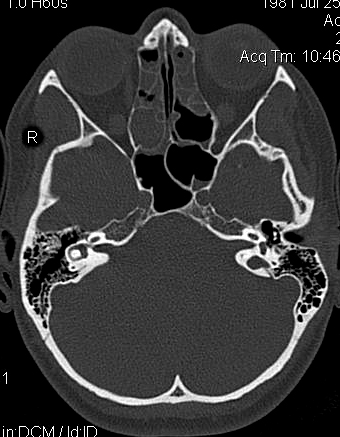

Fractura supracondílea de codo.

Fractura supracondílea de codo.Tras reducción y osteosíntesis.

Fractura supracondílea de codo. Tratamiento con agujas.